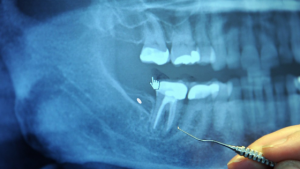

A Thai woman recently underwent corrective surgery to remove the tip of a dental instrument which was stuck in her gums for a total of five years. Apart from some minor symptoms, she did not know that this could cause a problem. She became aware of the underlying issue when her gums got infected.Krittika Rhittikhan is a 33-year-old patient from Mukdahan, a town in Thailand.Five years ago, she visited a hospital for the tooth extraction procedure. Apparently, the tip of the dental instrument broke off and remained inside her gums. At the time, she was told that the tip would automatically come off upon the healing of the socket.From then onwards, Krittika started experiencing an unexplained numbness in her tongue and lower lip. Earlier this year she realized that the tip was still embedded in her mouth. Unfortunately, she suffered from an infection in the gums surrounding the tip. She visited the Khon Kaen University's dental hospital to diagnose the same.The surgery was completed in half an hour. A team of four dentists performed the surgery after which a press conference was held. The woman expressed relief for the success of the surgery and thanked the operating dentists. She will require additional treatment for six months including vitamin supplements to promote the destroyed nerves.Dental instruments tend to be quite small in size which makes this error not so uncommon in the clinical practice. Experts urge us to seek help if there is any doubt that a part of an instrument has been left in the oral cavity. If there are symptoms such as pain, numbness or sensitivity after dental treatment, it is always better to follow up with your dentist to avoid a case like this gum mishap. Since the body tends to reject foreign particles, it's only a matter of time for such an error to result in inflammation and infection.